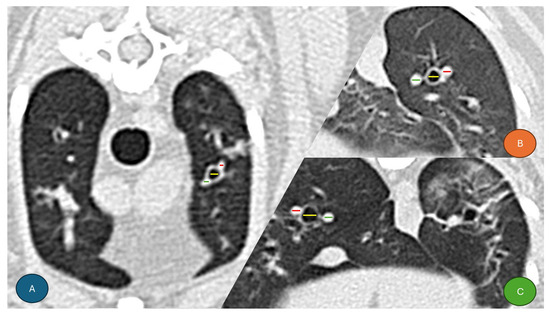

Respiratory diseases in dogs and cats are considered part of general internal medicine, or cardiology. Moreover, there are few veterinarians specializing in this field, with only a few specialized departments. Therefore, research on respiratory diseases in dogs and cats is sparse. For the definitive diagnosis of respiratory diseases, endoscopic examination and imaging tests, such as CT/MRI under general anesthesia, are often necessary. However, they are not always possible in all cases owing to the risk of general anesthesia and other facility issues. This is one of the reasons why there has been so little research on respiratory diseases. Although a few reports have been made in Europe and the United States, these results cannot necessarily be applicable to dogs and cats in Japan and other Asian countries because the popular breeds are different from those in Europe and the United States. Consequently, we call for research on respiratory diseases in dogs and cats, especially in non-European countries and the United States.